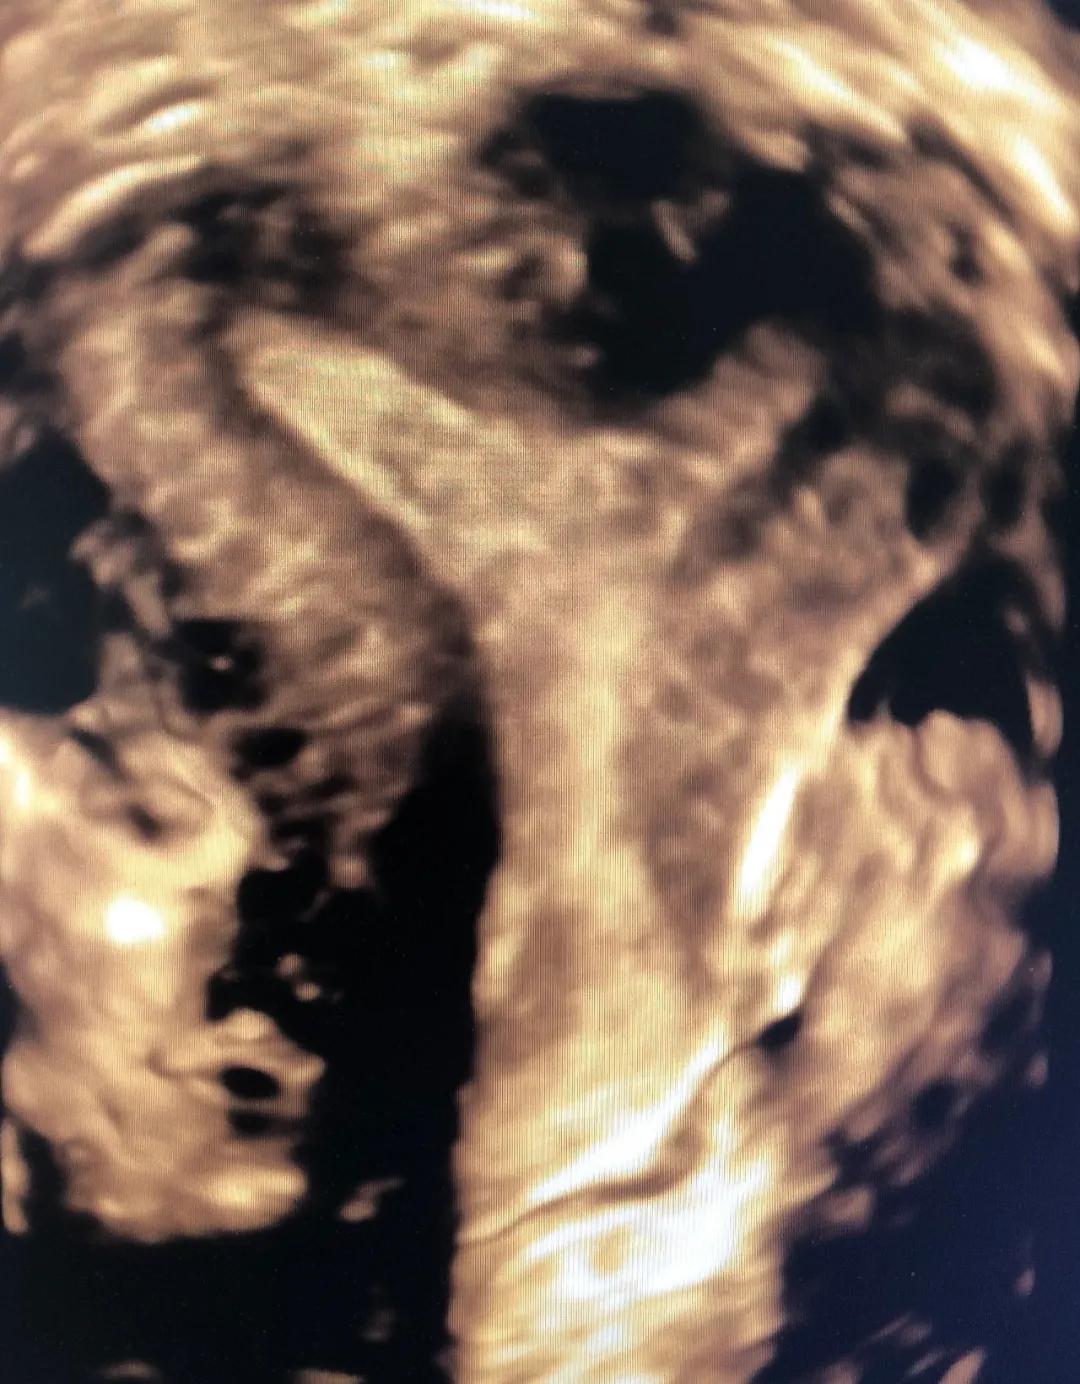

6月2日,一患者因外院超声诊断不全纵隔子宫来市妇幼院就诊,经常规妇科超声检查并未发现明显纵隔,与患者沟通后行经阴道四维超声检查,得到了清晰的图像诊断为弓形子宫,为妇科临床诊断提供了可靠依据。

腔内四维超声(4D-TVS)是在腔内二维超声基础上,利用计算机处理发展起来的新型超声诊断技术,可以提供更多的诊断信息,具有常规经阴道超声无法比拟的优势,立体直观,功能强大,可实现360度全方位无死角成像,大大弥补了单纯二维腔内超声的不足。

腔内四维超声检查可对先天性子宫畸形(完全或不完全纵隔子宫、弓状子宫、双角子宫、单角子宫、残角子宫等)、宫腔粘连、内膜息肉、粘膜下肌瘤进行诊断及鉴别诊断,还能清晰的观察到节育器的形态、位置,大大提高了超声在妇科疾病诊断中的准确率,为临床医生提供更准确的诊断信息,同时填补了我市在此项技术的空白。